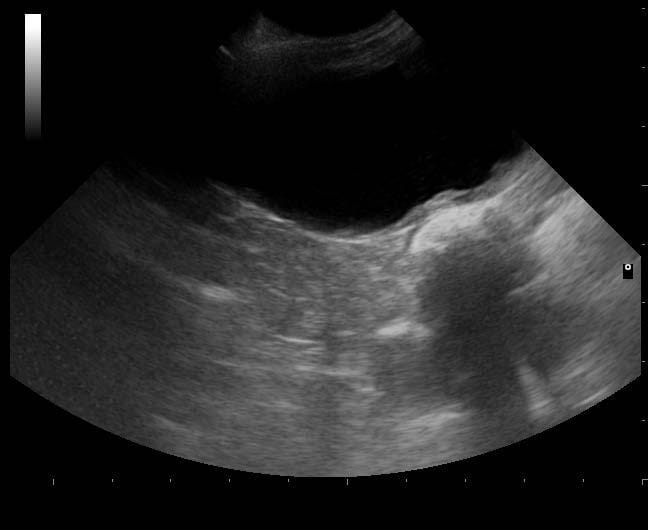

The entire bladder should be examined in longitudinal and transverse planes using a medium to high frequency transducer (greater than 7.5MHz), extending as far caudally as possible to examine the bladder neck. The bladder wall should be assessed systematically followed by the lumen (Figure 1). Ultrasonography should precede cystography.

The bladder wall thickness should be assessed fully. The far wall is usually most useful for this in ultrasounds. The mean bladder wall thickness is 2.3mm (in minimally distended bladders) to 1.4mm (in moderately distended bladders) in the dog (Geisse et al., 1997) and 1.3 to 1.7mm in the cat (Finn-Bodner, 1995).

Chronic cystitis usually produces wall thickening which is most pronounced cranioventrally, but in severe cases it can be generalised (Nyland et al., 2002).

Polypoid cystitis appears ultrasonographically as wall thickening with irregular multiple small masses that project into the urinary bladder lumen (Huynh and Berry, 2016). If large, they can appear pedunculated. They are typically seen in the cranioventral and craniodorsal bladder. Biopsy is required to differentiate between neoplastic and non-neoplastic lesions (Barrett, 2011; Figure 6).

Most mural masses are malignant tumours, but benign masses, polyps and adherent blood clots can also occur.

Transitional cell carcinoma is the most commonly diagnosed bladder tumour in the dog (Barrett, 2011). They are usually identified at the bladder neck as an attached filling defect of varying size using double contrast cystography (Thrall, 1998) or as a broad-based irregular mass of varying echogenicity on ultrasound. They are usually hypoechoic to the wall and they can also be multiple or pedunculate (Leveille et al., 1992; Figure 7).